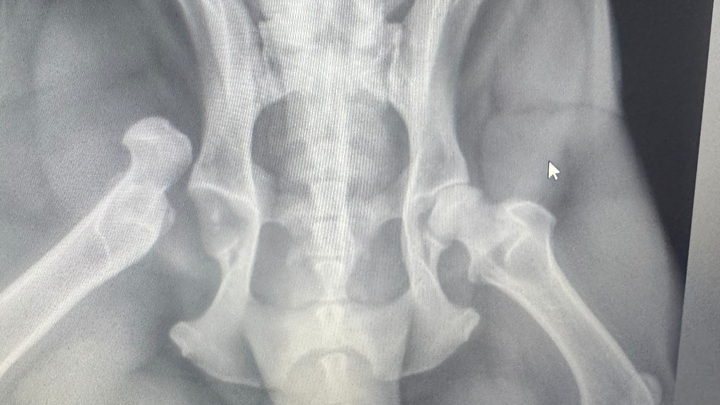

My beautiful dog, Rocky, who is three, got hit by a speeding car that never stopped. I tried my best to stand in the road, and the driver wouldn’t stop. I dove out of the way, but Rocky was hit. He needs emergency surgery.